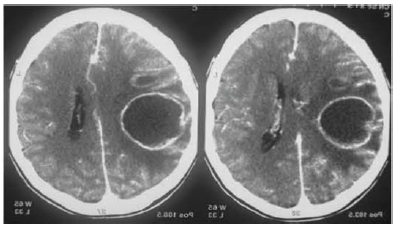

Um paciente de 32 anos de idade deu entrada no pronto-socorro com quadro de tosse e dor torácica de padrão pleural há cerca de um mês. Seu acompanhante refere que, há cinco dias, ele evoluiu com febre associada à cefaleia e, hoje, iniciou sonolência, afasia e hemiplegia à direita. O plantonista solicitou exames laboratoriais gerais, bem como tomografia computadorizada de crânio sem e com contraste. Após o resultado do exame de imagem mostrado a seguir, solicitou avaliação da neurocirurgia.

enunciado 323612-1

Mário G. Siqueira. Tratado de neurocirurgia. 1.ª ed. 2016.

Considerando esse caso hipotético e as características radiológicas do principal diagnóstico em questão, assinale a alternativa incorreta.